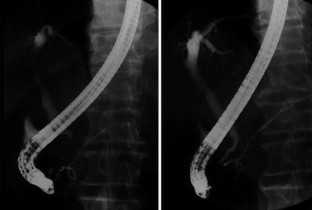

Change in pancreatic size showed no significant difference between the therapies after 2 weeks of treatment. Significant improvement of lower bile duct strictures after 2 weeks of treatment and that of immunoglobulin values within 6 months were shown with both therapies. However, steroid pulse therapy showed significant improvement of γ-guanosine triphosphate (GTP) in 2 weeks and of alanine aminotransferase (ALT) in 2 and 8 weeks, compared with oral steroid therapy. Moreover, there was one patient in whom the lower bile duct stricture was not improved by oral steroid therapy, but it did show improvement with steroid pulse therapy.

Initial steroid pulse therapy is a beneficial alternative to oral steroid therapy for the improvement of bile duct lesions. In future, the accumulation of a larger number of patients receiving steroid pulse therapy is needed, and prospective studies will be required.